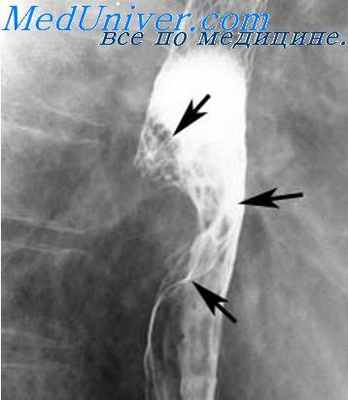

Очень типичной является рентгенологическая картина заболевания. Этот широкодоступный метод является основным при постановке диагноза. Важным дополнением служит эндоскопическое исследование, а также ЗЗОФАГОМАНОМЕТРИЯ – исследование, направленное на измерение давления в пищеводе и в нижнем пищеводном сфинктере.

Пищевод нормального диаметра (по стрелке) при рентгенологическом исследовании.

Кардиоспазм 3 и 4 стадии (пищевод заполнен контрастным веществом)